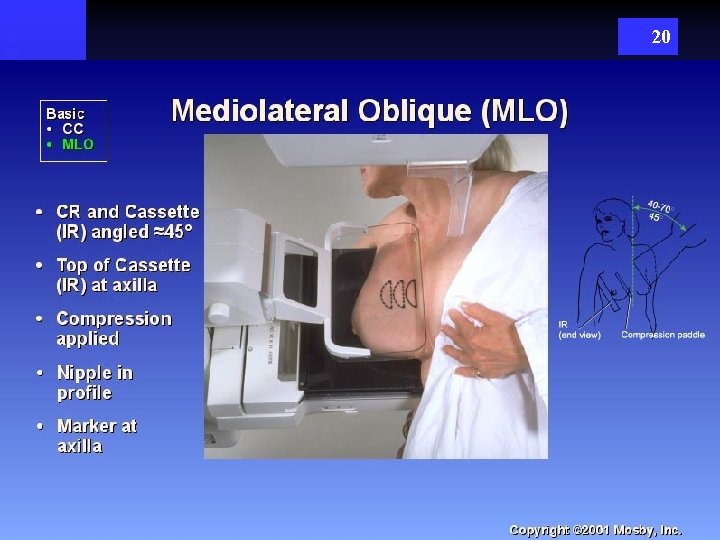

20